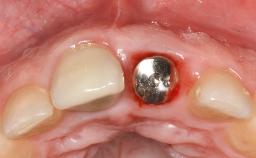

A 37-year-old male patient was referred to the Department of Periodontology at the University of Bern, Switzerland, by a private dentist. Tooth 21 had been lost due to trauma and had been replaced with an implant and a cemented single crown. The tapered-effect tissue-level implant had a diameter of 4.1 mm, a length of 12 mm, and a sandblasted and acid-etched (SLA) surface (Straumann Dental lmplant System; Institut Straumann AG, Basel, Switzerland). The metal-ceramic crown had been cemented permanently, leaving a submucosal gap between the implant shoulder and the crown margin. Absence of marginal bone loss apical to the polished transmucosal neck of the implant could be observed .